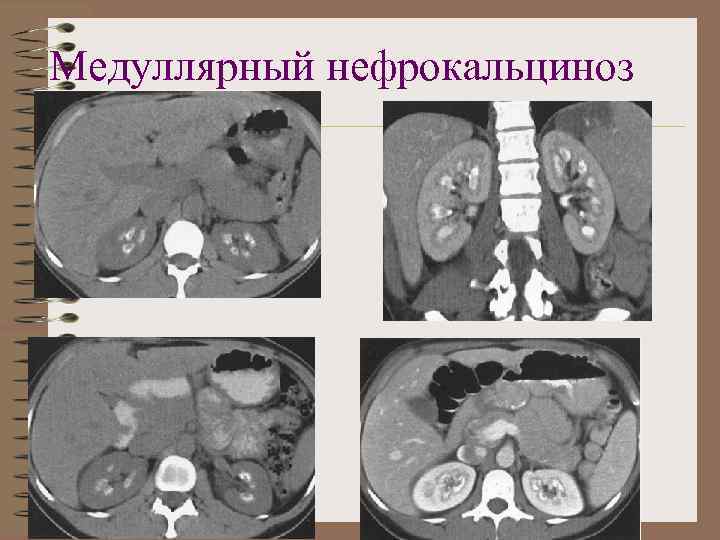

Медуллярный нефрокальциноз